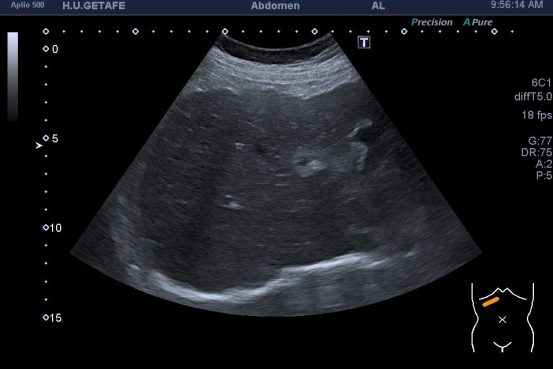

De la imagen 1 a 3 ves un hígado afectado por una cirrosis hepática. En ella vas a ver un tejido anormalmente heterogéneo, parcheado en ocasiones, como con «grumos», a veces muy pequeños, otras veces más grandes. Son los nódulos de regeneración. Cuando las células del tejido hepático se mueren son sustituidas por tejido cicatricial. Puedes ver el borde hepático abombado. Los cambios en la ecogenicidad son variados, te he decimos algunos, no me interesa contarte esto, me interesa que compares la imagen 1,2 y 3 con la imagen 4 y veas patología y normalidad del parénquima hepático. Muchas veces una imagen vale más que mil palabras, lo sé…